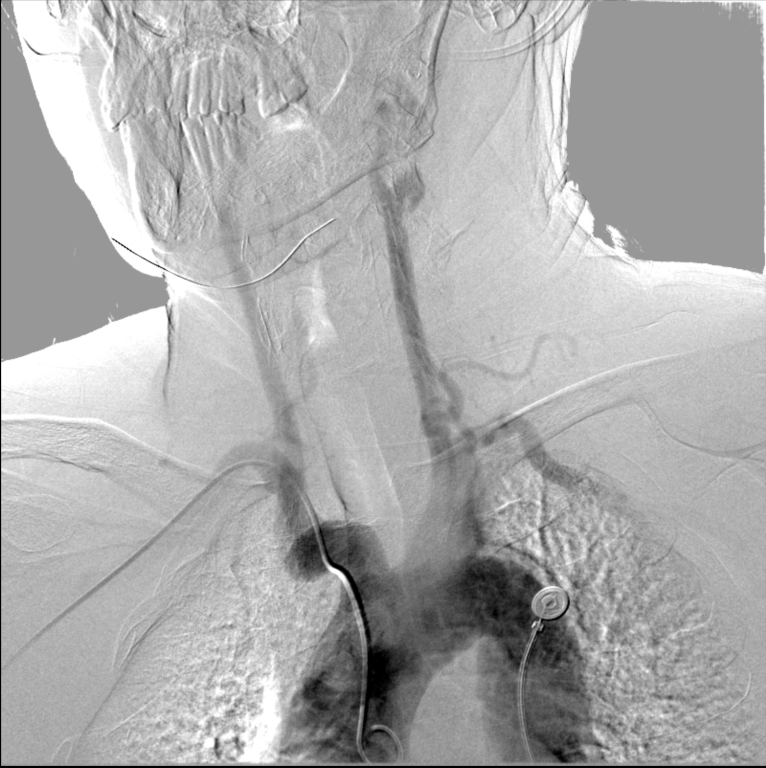

右侧桡动脉穿刺成功后置入6F桡动脉鞘,完成血管造影后更换6F 90cm lonAccess长鞘。泥鳅导丝引导下同轴送入6F 90cm lonAccess长鞘+5F 125cm Simmons II,越过迂曲的右锁骨下动脉,塑形成功并到达左侧颈总动脉。

康德莱医械5F 125cm Simmons II+康德莱医械6F 900mm lonAccess长鞘同轴送达左侧颈总动脉末端。